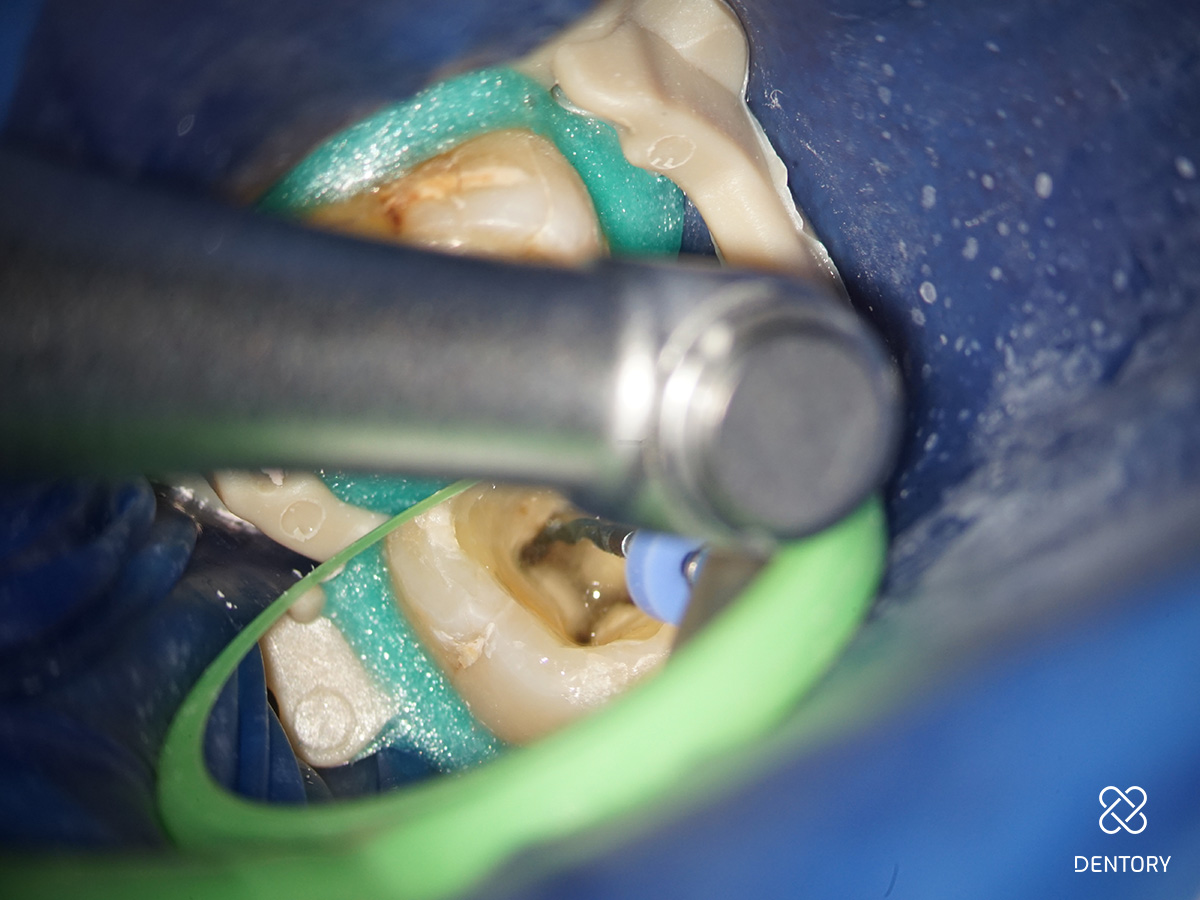

Abbildung 4

Nach jedem Einsatz im Kanal ist die Feile visuell auf Deformationen zu überprüfen.